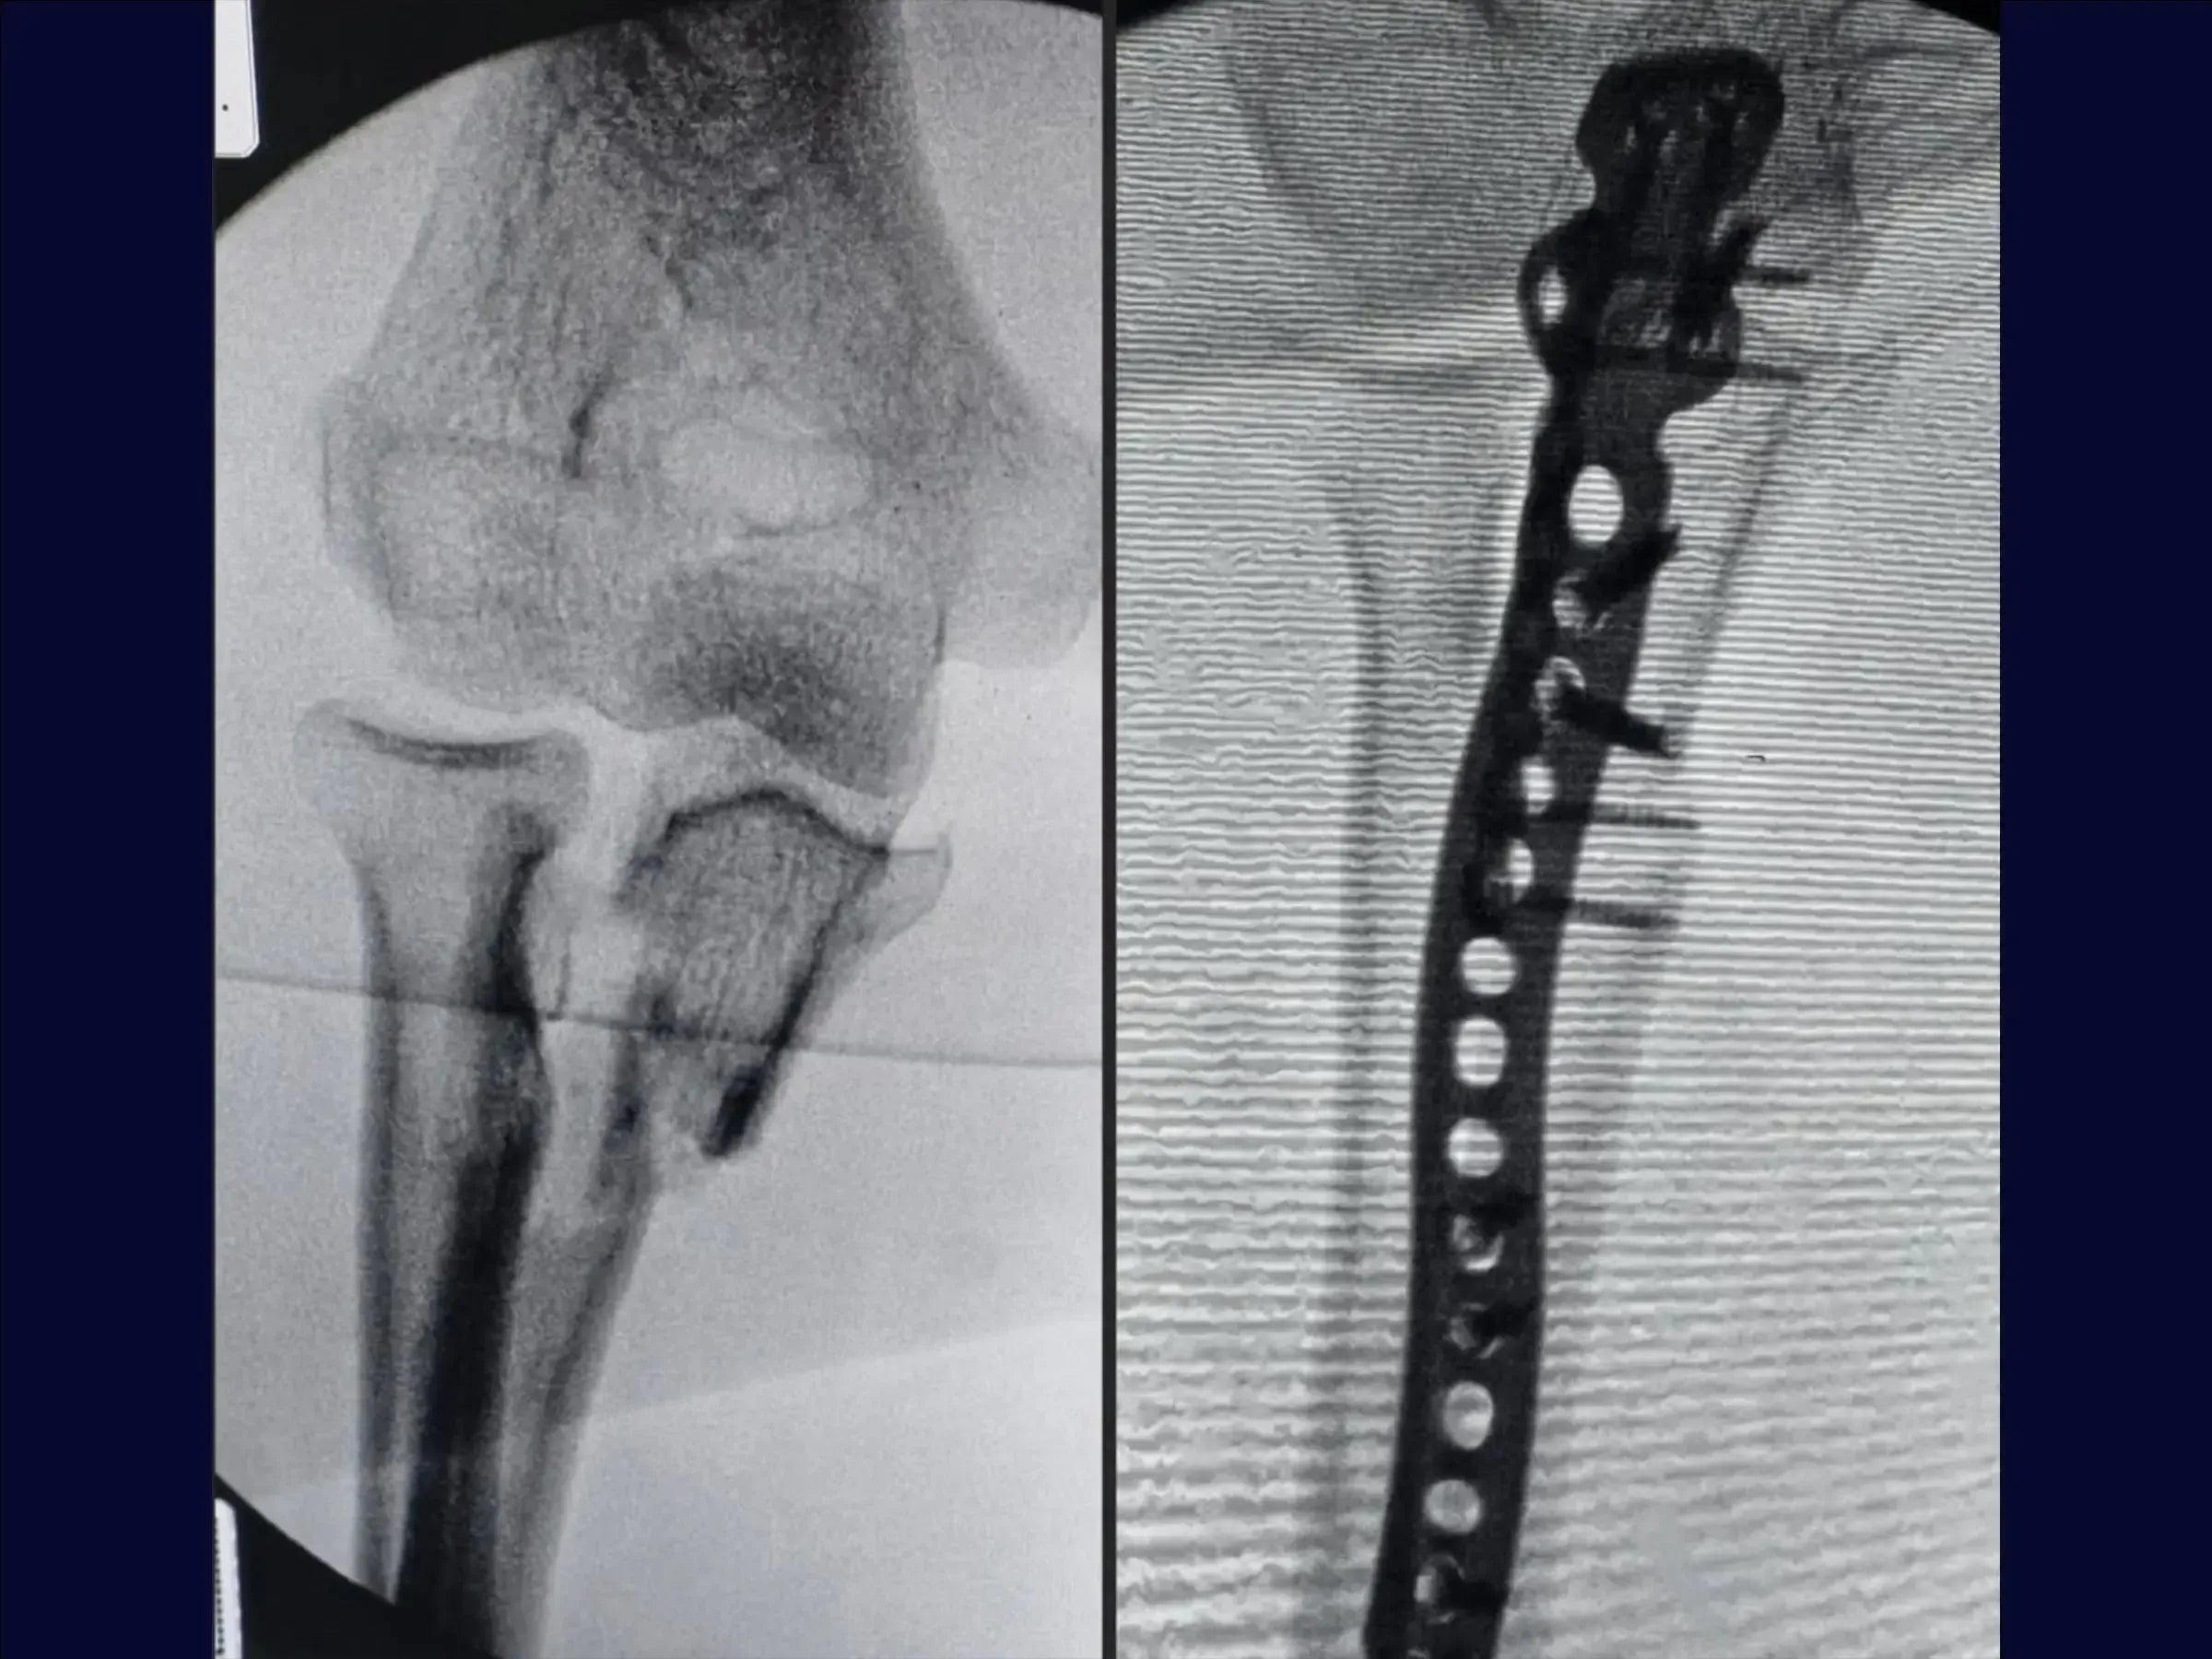

- Treatment of transolecranon fracture-dislocation of the elbow (Monteggia variant).

- Reduction and fixation of multifragmentary proximal ulnar fractures.

- Reduction of the Ulna: Fracture reduction with Kirschner wires.Lateral fragment fixation with a mini-fragment plate, enabling the use of a long plate on the olecranon.

- Finalization and Stabilization: Pull-out tying and definitive fixation with a long locked plate on the ulna metaphysis, ensuring joint stability.